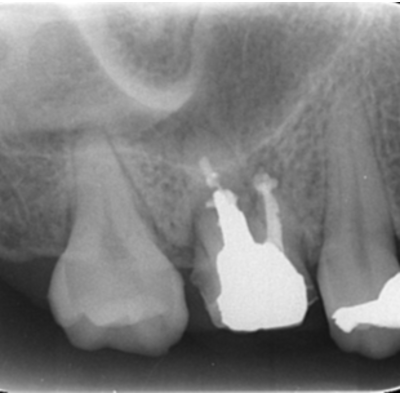

移植手術3ヶ月後のレントゲン画像

移植3ヶ月後。

歯根周囲に透過像を認めるが動揺などはなく、歯周ポケットも形成されていなかった。

移植12ヶ月後のレントゲン

移植12ヶ月後。セラミッククラウンで歯冠を修復した。

デンタルX線写真では透過像もほぼ消失している。